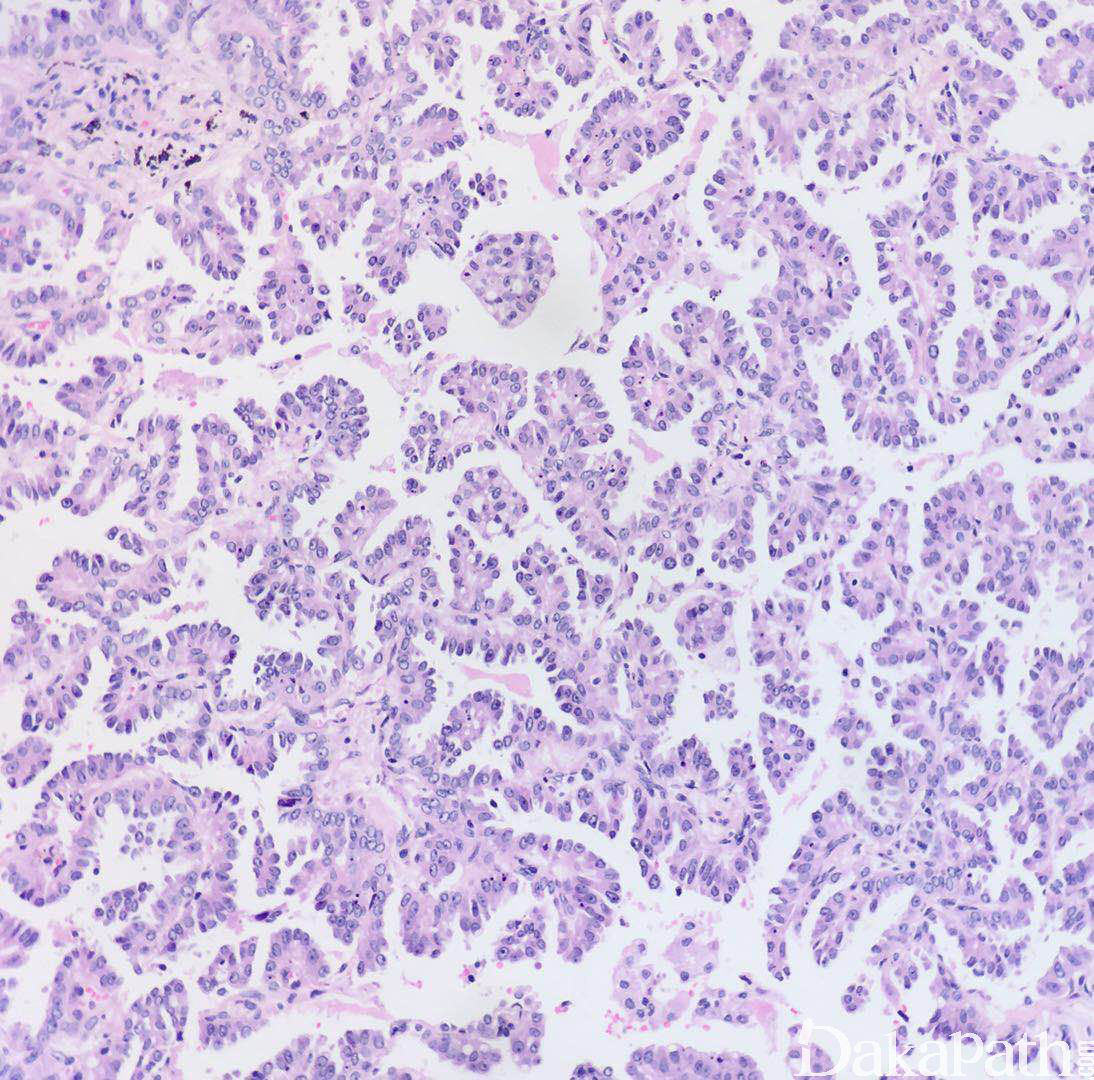

肺乳头状腺癌

Lung Papillary Adenocarcinoma

主要由有纤维血管轴心的乳头状结构构成;

不需要间质浸润的证据;

如肿瘤性腺泡或肺泡腔充满乳头或微乳头,应分类为乳头型或微乳头型腺癌;